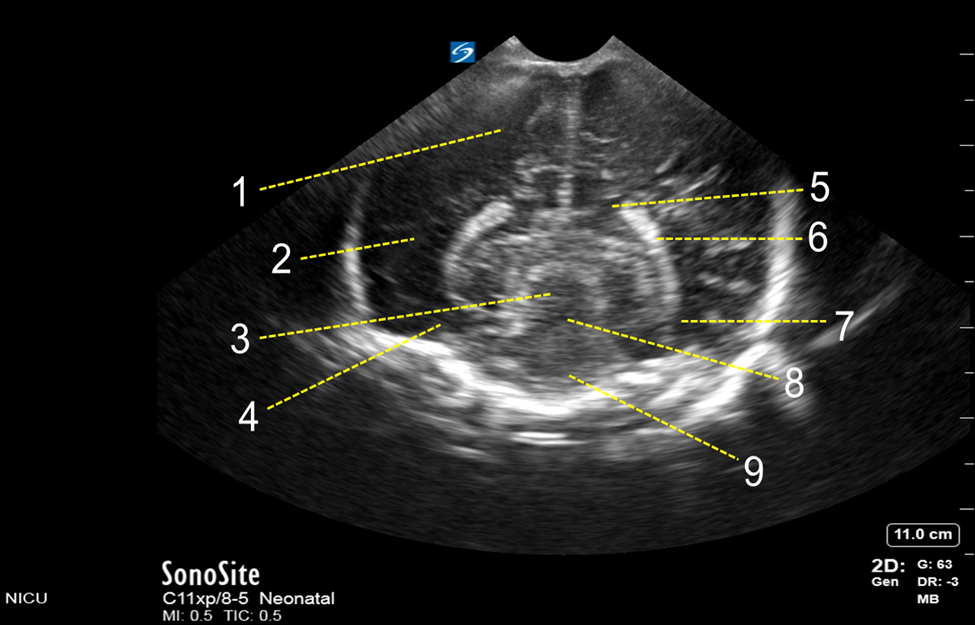

Neonatology Posterior Fontanelle Superior Coronal View Image

1. Occipital Lobe

2. Parietal Lobe

3. Mesencephalic Aqueduct

4. Temporal Lobe

5. Occipital Horn of Lateral Ventricle

6. Choroid Plexus

7. Body of Lateral Ventricle

8. Mesencephalon

9. Interpeduncular Cistern